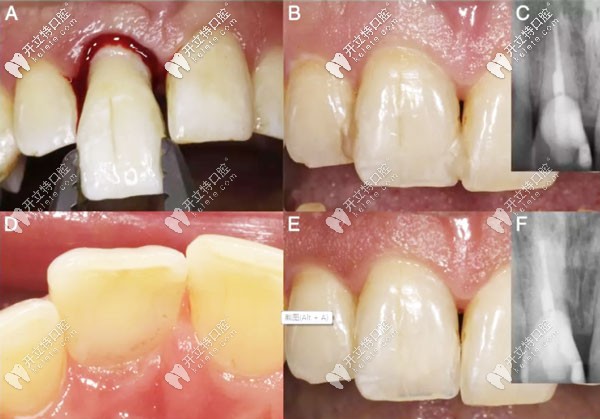

意向性牙再植術(shù)的預(yù)后示意圖